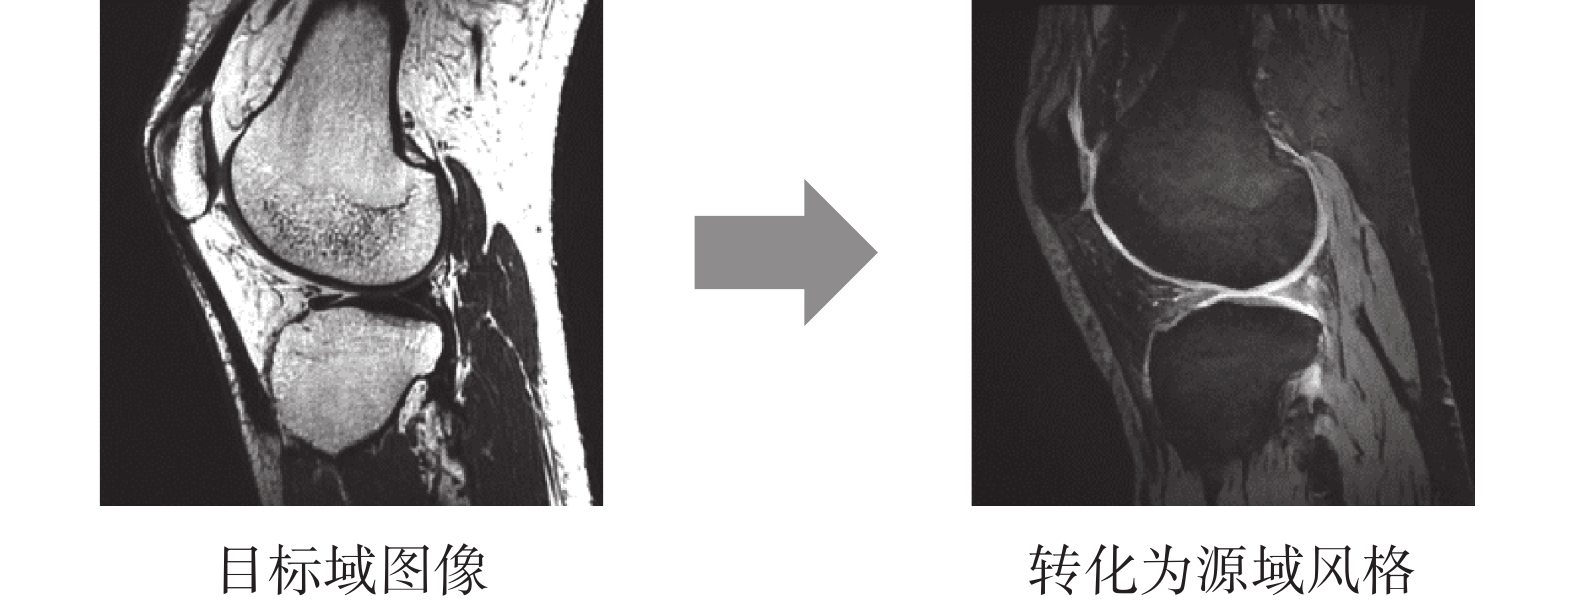

其次使用Zhu等[12]提出的CycleGAN圖像級域自適應網絡,將不同類型的MR圖像相互轉換。具體為使用通過CycleGAN訓練好的生成器,將目標域圖像轉換為源域圖像風格,并輸入使用源域數據訓練的分割網絡。本文遵循之前研究中CycleGAN的實驗參數設置,訓練生成器和鑒別器。

我們在測試集中隨機選取兩張圖像進行對比分析,所提方法與三種已有方法的分割結果如圖6所示。由于存在域轉移問題,直接使用由源域數據訓練的分割網絡對目標域圖像進行分割,無法對股骨和脛骨進行有效分割,分割區域不完整。Zhu等[12]提出的圖像級域自適應方法使用CycleGAN將目標域圖像轉換為源域圖像風格,如圖7所示,再使用由源域數據訓練的分割網絡進行分割,能有效改善分割結果,但假陽性區域過多。使用Panfilov等[17]提出的特征級域自適應方法后,分割區域存在較多缺失。而本文所提的特征級域自適應方法的分割結果與手工分割結果最為接近。